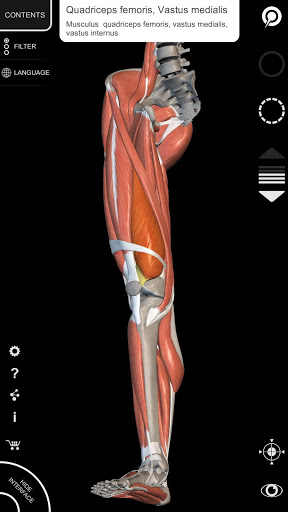

"Anatomy 3D Atlas" memungkinkan Anda mempelajari anatomi manusia dengan cara yang mudah dan interaktif.

Melalui antarmuka yang sederhana dan intuitif, Anda dapat mengamati setiap struktur anatomi dari sudut mana pun.

Model 3D anatomi sangat terperinci dan memiliki tekstur hingga resolusi 4k.

MODEL ANATOMI 3D

• Sistem muskuloskeletal

saraf • Sistem pernapasan • Sistem pencernaan • Sistem urogenital (pria dan wanita) • Sistem endokrin • Sistem limfatik • Sistem mata dan telinga FITUR • Antarmuka yang sederhana dan intuitif • Putar dan perbesar setiap model dalam ruang 3D • Opsi untuk menyembunyikan atau mengisolasi satu atau beberapa model yang dipilih • Filter untuk menyembunyikan atau menampilkan setiap sistem • Fungsi pencarian untuk menemukan setiap bagian anatomi dengan mudah • Fungsi penanda untuk menyimpan tampilan khusus • Rotasi cerdas yang menggerakkan pusat rotasi secara otomatis • Fungsi transparansi • Visualisasi otot melalui tingkat lapisan dari yang superfisial hingga yang terdalam • Dengan memilih model atau pin, istilah anatomi terkait akan muncul • Deskripsi otot: asal, • Tampilkan/ Sembunyikan antarmuka UI (sangat berguna dengan layar kecil) MULTIBAHASA • Istilah anatomi dan antarmuka pengguna tersedia dalam 11 bahasa: Latin, Inggris, Prancis, Jerman, Italia, Portugis, Turki, Rusia, Spanyol, Mandarin, Jepang, dan Korea • Istilah anatomi dapat ditampilkan dalam dua bahasa secara bersamaan PERSYARATAN SISTEM • Android 8.0 atau yang lebih baru, perangkat dengan RAM minimal 3GB Reversi